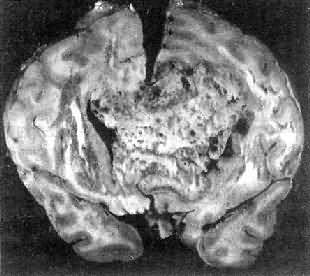

肉眼观,肿为数厘米的结节至巨大块状。分化较好的肿,境界不清;而分化程度较低的肿则境界分明。体灰白色。质地视肿内胶质纤维多少而异,或硬、或软、或呈胶冻状外观,并可形成大小不等的囊腔。由于肿的生长、占位和邻近脑细胞的肿胀,脑的原有结构因受挤压而扭曲变形(图16-23)。

图16-23 星形胶质细胞

左大脑半球肿胀,肿边界不清,部分呈胶冻状